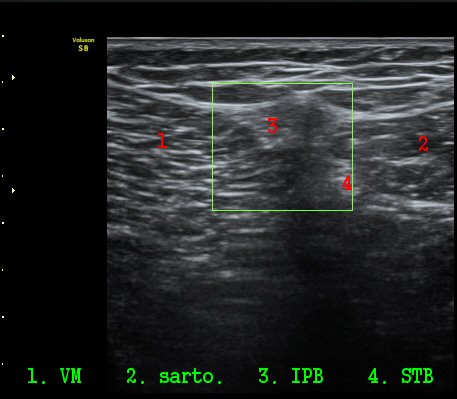

ŽÃËÀÚ¸¦ ¸»´ÜÀ¸·Î À̵¿ÇÏ´Ï º¹Àç½Å°æÀÌ ½½°³°ñÇϰ¡Áö¿Í  ºÀ°ø°¡Áö(sartorial branch)·Î

°¥¶óÁö´Â °ÍÀÌ °üÂûµÇ°í(»çÁø 3, 4, 5) µ¿¿µ»ó È­¸éÀ¸·Î º¸¸é ´õ¿í ¶Ñ·ÈÇÏ´Ù(÷ºÎ ÆÄÀÏ 1)